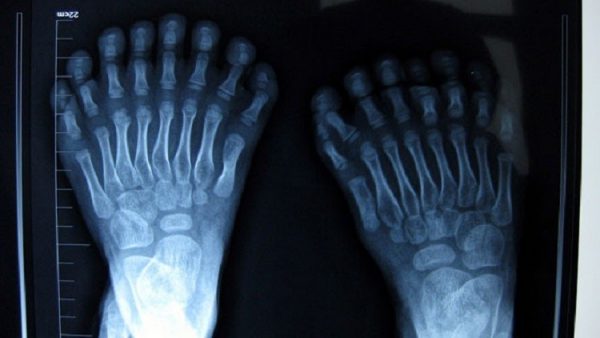

ذكرت وسائل إعلام أن طفلا صينيا ولد بـ 16 إصبعا على القدمين و15 أخرى على اليدين، في مشهد صادم ونادر.

وأنجبت الأم هذا الطفل، واسمه “هونغ هونغ”، في مقاطعة خنان شرق الصين، في شهر يناير من العام الجاري، ومنذ ذلك الحين يسعى والداه إلى إجراء عملية جراحية للطفل المصاب بمرض (Polydactyly).